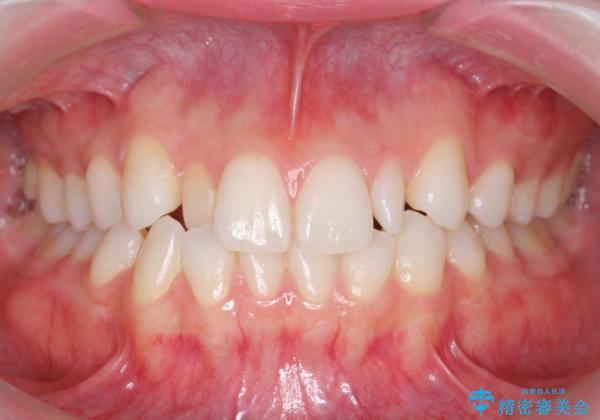

- 前歯のがたつきと小さな歯の形を治したいと来院。

いきなりセラミックでかぶせるよりも手間をかけた分、自然な仕上がりになっています。

先に矯正治療をすることで、下の前歯を内側に入れることができ、上の歯のセラミックの幅や厚みを取ることができました。